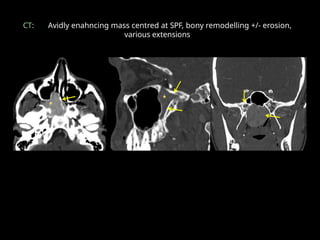

CT: Avidly enahncing mass centred at SPF, bony remodelling +/- erosion,

various extensions

CT: Avidly enahncingmass centred at SPF, bony remodelling +/- erosion, various extensions • q